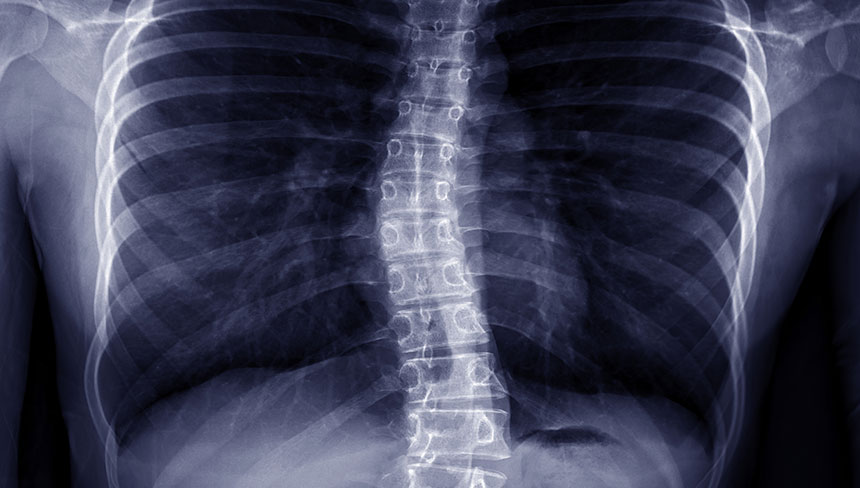

Does your child have scoliosis? We understand how much it can interfere with their daily tasks such as standing, sitting, walking, or even breathing. Finding relief from scoliosis can be a daunting journey with limited treatment options.

Living with scoliosis can have a tremendous impact on your child's life, from their emotional state to their ability to perform mundane tasks. Scoliosis is one condition that should be actively managed, or it may worsen if left untreated.

So, what exactly can happen if scoliosis goes untreated?